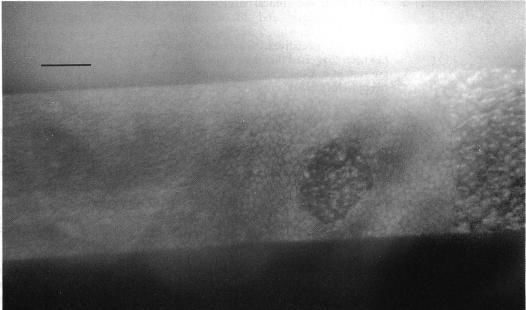

虹膜角膜内皮综合征和后极性多形性营养不良的鉴别特征:内皮细胞镜检查的价值

Distinguishing features of the iridocorneal endothelial syndrome and posterior polymorphous dystrophy: value of endothelial specular microscopy.

The literature suggests that posterior polymorphous dystrophy (PPD) may show features such as iridocorneal adhesions, glassy membranes, and pupillary ectropion which are typically ascribed to the iridocorneal endothelial (ICE) syndrome. This complicates diagnosis. PPD, unlike ICE, is familial, and ICE, unlike PPD, is usually progressive and frequently complicated by glaucoma: thus it is important to distinguish between them. To determine whether this could be achieved by specular microscopy, since the posterior corneal surface is abnormal in both conditions, 57 cases of ICE and 44 of PPD were repeatedly examined and photographed with the specular microscope. Progressive and/or static morphological features of the corneal endothelium and Descemet's membrane were found that were specific for each condition. Specular microscopy can thus provide a definitive diagnosis of ICE or PPD even in uncertain cases.

文献表明,后极性多形性营养不良(PPD)可能表现出虹膜角膜粘连、玻璃样膜和瞳孔外翻等特征,这些特征通常归因于虹膜角膜内皮(ICE)综合征。这使得诊断变得复杂。与ICE不同,PPD是家族性的,而与PPD不同,ICE通常是进行性的,并且经常并发青光眼:因此区分它们很重要。为了确定这是否可以通过镜面显微镜检查来实现,由于在这两种情况下角膜后表面均异常,因此对57例ICE患者和44例PPD患者进行了多次镜面显微镜检查并拍照。发现了角膜内皮和Descemet膜的进行性和/或静态形态学特征,这些特征对每种情况都是特异性的。因此,即使在不确定的病例中,镜面显微镜检查也可以对ICE或PPD做出明确诊断。